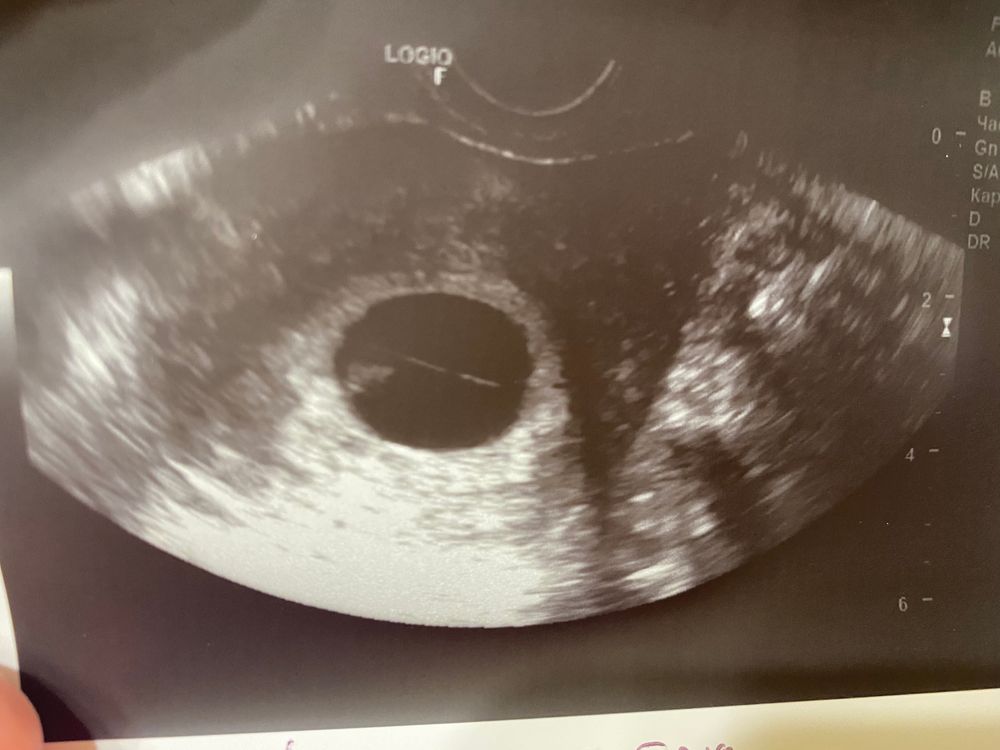

Сегодня была на узи, срок поставили 7 недель, ктр 11мм, включили сердечко подслушали ❤️

но единственное врач увидел амниотический тяж, сказал, что ничего страшного, главное, пусть на скрининге в 12 недель посмотрят. начиталась в интернете страшилок, теперь места себе не нахожу. Подскажите, было у кого-то подобное, какова вероятность, что рассосётся ?